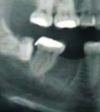

Angulation?

mesial

40

horizontal

41

distal

42

vertical

43

Angulation

transverse

44

aberrant

why would we want to measure depth of a 3rd molar in relation to the 7

gives an indication of the amount of bone removal required

46

if crown of 8 related to crown of 7

superficial depth

47

if crown of 8 related to crown and root of 7

moderate depth

48

if crown of 8 related to root of 7

assess radiographically

superficial distal impaction

50

horizontal moderate impaction